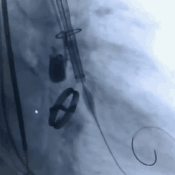

3. 术中实行的20球囊的预扩,AV26瓣膜的释放,瓣膜释放后发现还有展开的余地,故进一步选择23的球囊进行后扩使人工瓣膜更贴合主动脉根部结构。

瓣膜定位

瓣膜缓慢释放

23mm球囊后扩张

瓣膜释放后造影评估